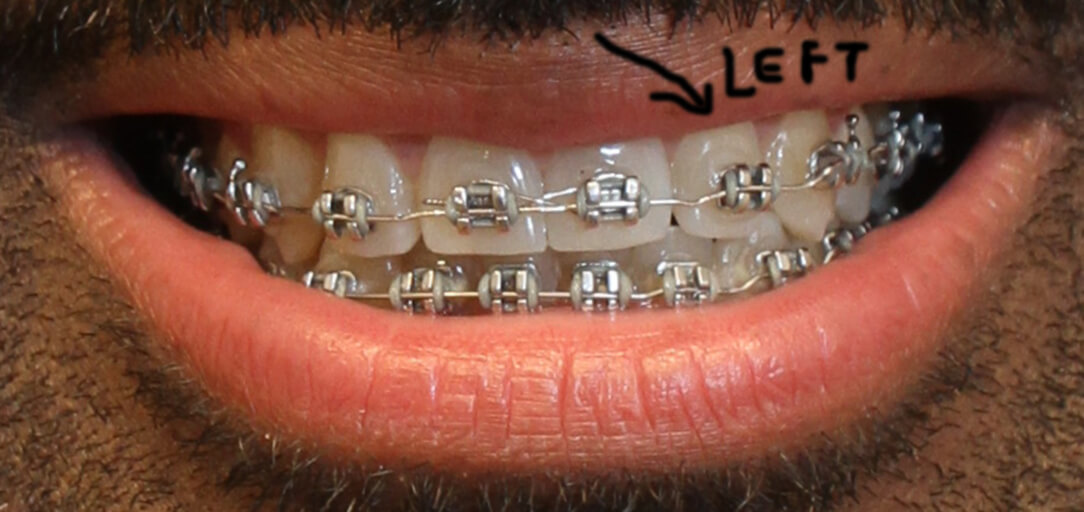

Good Morning, I have had braces for 20 months, but my orthodontist told me I would only need them 3 months! I basically was a relapse case. I had Invisalign in 2007-2008 to close a gap in my front teeth, and a permanent retainer was affixed to the back of my front four teeth to keep the gap closed. My current orthodontist finished my Invisalign case with a Howley retainer and elastics, after I initially had gone to a general dentist to start my Invisalign case. I was very pleased with my smile at the conclusion of my Invisalign case in 2008! In early 2016, my gap re-opened after my permanent retainer broke. It only took around two weeks for the gap to reopen upon the retainer breaking! I went to get the retainer repaired, and the gap had re-opened too wide for my orthodontist to close with finger pressure. Therefore, my orthodontist recommended a Howley retainer to try to remedy the problem. The Howley retainer closed the gap, but the top teeth did not meet well with the bottom teeth, causing malocclusion and 'hitting' of the two rows of teeth. Therefore, traditional metal braces were introduced as a solution. Again, my orthodontist said I would only need 3 months to conclude my braces treatment! It has now been 20 months! My braces treatment started in September 2016. At the three-month mark, I thought my bite was good, and my teeth were looking pretty good. About 5 months into treatment, I noticed there was a space forming in between my two left canine teeth. That caused the left side of my smile not to 'fit' together. It made my smile look uneven. My orthodontist tried to remedy this by making me wear elastics off on and on for over 6 months (between February 2017 - October 2017), but the space did not close as I liked by October 2017. They don't fit together much better now. At this time in October 2017, my orthodontist was talking about doing an impression! As much as I wanted to take my braces off at this time in October, after going 4 times the amount of time I thought I would be in braces (12 months at that time), I knew I would not be pleased with this result. Due to my dissatisfaction, My orthodontist then instituted other elastic configurations to see if this would help, but the desired result still did not happen. I visited other orthodontists for a second opinion on how to close the space better, and they recommended adjusting brackets to put more force on the teeth at better angles to make them fit. I mentioned moving brackets to my orthodontist. However, for some reason, my orthodontist was against moving brackets, always saying "I don't need to do that. I can bend the wire." She insisted that only young orthodontists use the adjusting of brackets as a method, particularly because that is how they were taught, and they aren't familiar with bending wires, as she, an older orthodontist, is familiar. She said that younger orthodontists aren't trained to bend wires now, as she was taught. My orthodontist finally begrudgingly moved the bracket on my top canine higher on the tooth, around early March 2017, after I asked for a third time. I did not want the bracket moved higher, but lower, as I wished to tilt the crown of the tooth more upward. However, my orthodontist did it her way. Her moving the bracket higher caused the top canine to come down in an unsightly fashion, almost at an angle. It also exacerbated the situation, as it made the space between the canines much bigger. It stayed like this over two months inexplicably (this is when I started to get other second opinions), and she just closed the space in late April, with an adjustment. The photo I have posted is how my teeth look now. I wanted to post photos that show change from the beginning until now, but there seems to be one-photo limit on this site. In the current photo, I still don't think my left canines meet well, and the top canine still comes down at a less than aesthetic angle and sort of just overlaps the bottom canine, rather than 'fitting' it. Another issue that makes my smile look uneven is that my left and right incisors are not level with each other. You can see that in the photo. My orthodontist has not been able to successfully address this either. She has tried to use a powerchain to bring the bottom teeth inwards, so the top teeth can come down more, and thus the left incisor can be moved down, but the powerchain has not worked. To sum up, my orthodontist's 'bending of the wires' has not moved my teeth into the desired position. It's really as if there has been hardly any real noticeable movement from February 2017 to now May 2018. I would think from all of that time to perfect, my teeth would look amazing now, but they don't. If you look at my photo, the spaces mentioned above make the left side of my teeth look a little jagged and 'open'. The right side of my smile is well spaced, and 'closed' from the front. What I mean by 'closed' is that you only see white teeth connected, and no spaces or fault lines. However, there are still spaces in between teeth on the left side, namely between the left incisor and the left front tooth at their bases, and the left canines are not meeting flush, but overlapping moreso. I simply want the left side of my smile to match the right side of my smile, particularly from the front. I must note that from my side profile, there are still some fault lines from the side, where teeth don't seem to meet the best way as well. However, I could be willing to deal with this if the teeth can be fit better from the front. My orthodontist doesn't seem to have the ability to move brackets strategically and does not seem flexible enough for me as a patient. It feels like every time I have an appointment, she is just doing trial and error, with no real conclusive plan on how to solve my problem. This has been going on for over a year in regards what I felt were easy problems to solve! I am thinking of changing to an orthodontist whom I consulted for a second opinion, whom uses more advanced techniques than my current orthodontist. I am beyond frustrated and fatigued of wearing braces. I am an older man, at 38 years old, and only agreed to get braces because I was told my initial issues (closing a gap between my two front teeth, and re-positioning my bottom teeth) would only take 3 months to treat, and there were no other issues. My orthodontist has non-urgently taken nearly 8 times that amount of time, only to leave me with dissatisfaction. I would like to go to another orthodontist. However, I don't want to pay out more money if this is an issue that can't be remedied any more than it already has. What do you recommend from looking at my picture? The other orthodontist whom I consulted for a second opinion, recommended wearing 'inside-out' rubber bands to 'tuck' the top-left canine in better and have it meet better with the bottom, and then proceed with bracket adjustment to finish the space closure for a better fit. To allow the left incisor to come down more to be level with the right incisor, they recommended potentially doing interproximal reduction on the lower four teeth to create more room to angle them inwards, which would allow the top row to come down more and look more even with the bottom (so my smile would look more even overall). Thus, the left incisor could be brought down more and and be positioned level with the right one, without malocclusion and hitting on the bottom teeth, which has been a problem as well. She said the interproximal reduction would also allow the top two front teeth to rest better on the bottom teeth and not hit too hard, which would help my gap stay closed better than the current position would. This would help avoid a second relapse. Do you think these methods and suggestions from the second orthodontist could work to fix my issue(s)?